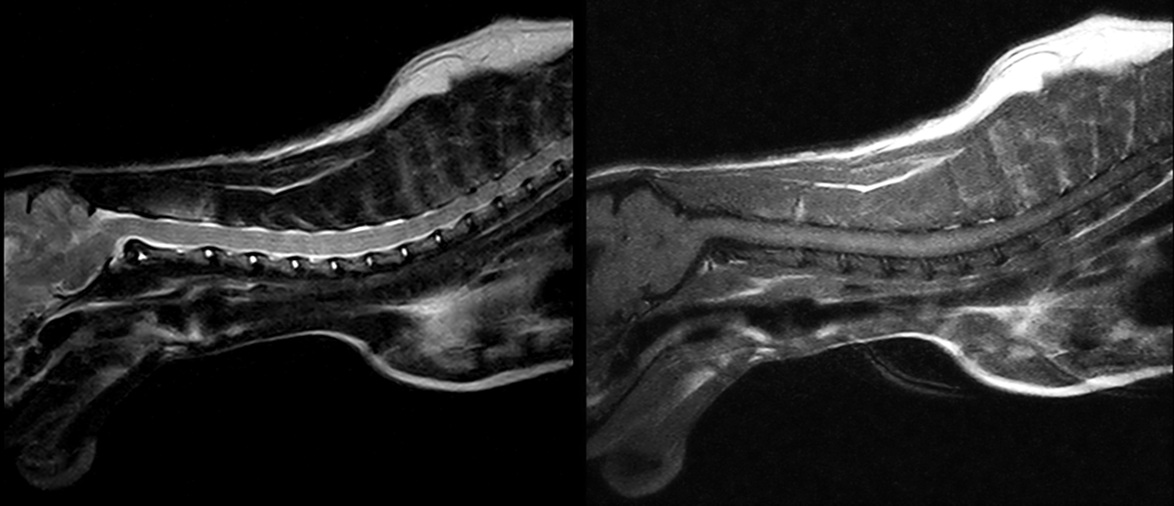

Деталізований знімок шийного відділу хребта кота у сагітальній проекції: чітка візуалізація спинного мозку та міжхребцевих просторів